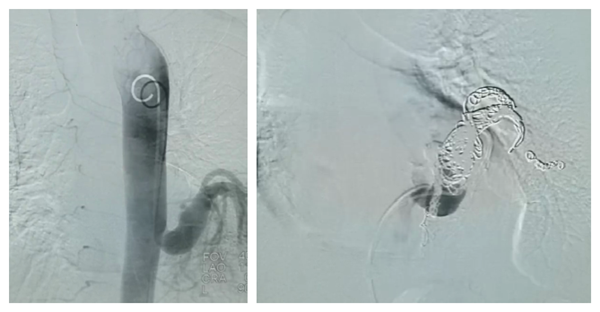

成人肺隔离症经皮动脉栓塞

伴着120呼啸的警笛声,一名45岁男性患者被急诊送入我院,此患者因在外院治疗效果不佳,故以“间断咯血15天,加重1天”之主诉来我院。急诊医师接诊后立即通知急诊介入团队,根据CTA相关检查,明确诊断为肺隔离症,该例病例由胸主动脉供血,供血血管直径达18-21mm。我科介入团队与影像科介入团队共同制定诊疗方案,决定采用经皮弹簧圈联合NBCA(氰基丙烯酸异丁酯)栓塞治疗该例肺隔离症患者,经过两个团队的通力合作,手术过程非常顺利,患者安返病房。

栓塞前与栓塞后